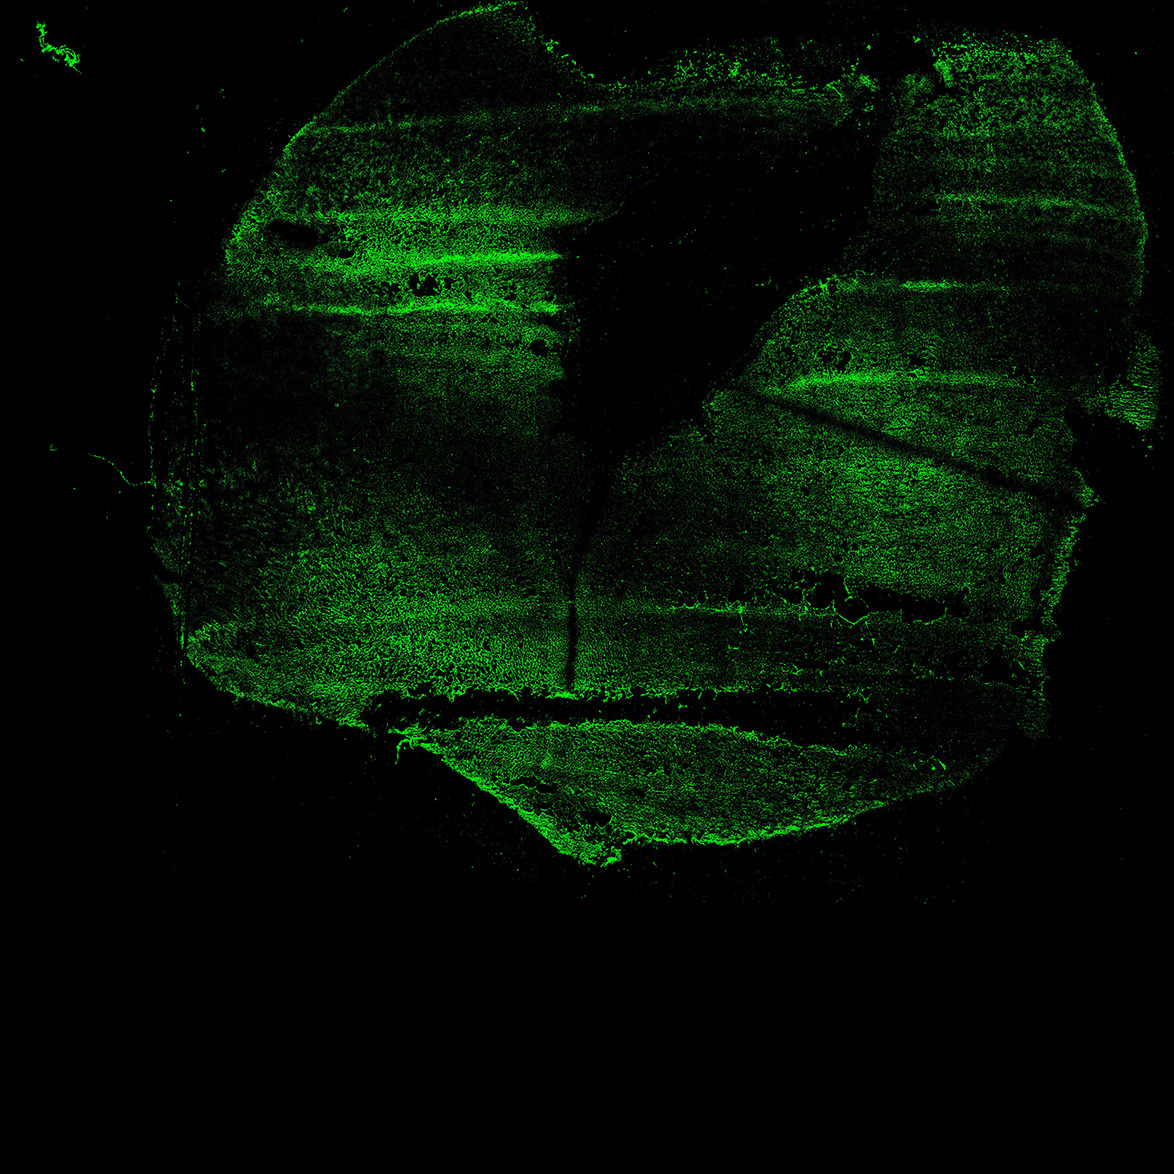

MAP2

11PCW human midbrain